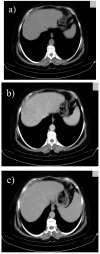

Hepatocellular carcinoma is a major health issue, ranked the fifth most common tumor and currently being responsible for a third of the cancer-related deaths globally, with an ever-increasing number of fatalities. Current advances in contrast-enhanced imaging techniques such as contrast-enhanced ultrasonography, multi-detector computed tomography and diffusion-weighted magnetic resonance imaging are improving the rate of hepatocellular carcinoma diagnosis. Contrast-enhanced ultrasonography has widely become the first choice in liver tumor assessment, as it is faster, simpler and safer than other forms of diagnostic imaging. On the other hand, cross sectional computed tomography is frequently employed when a hepatic formation is suspected of malignancy and allows a more accurate characterization of lesions through multiphasic multi-detector computed tomography technology. Diffusion weighted magnetic resonance imaging represents another addition to the wide range of diagnostic and prognostic techniques available for patients with hepatocellular carcinoma and is currently regarded as one of the best tools for the characterization of these lesions. Furthermore, groundbreaking biomarkers for hepatocellular carcinoma are being discovered, although alpha-fetoprotein remains one of the most frequently used serum test in the early stages. Nonetheless, further advances are required for the detection of small liver carcinomas.